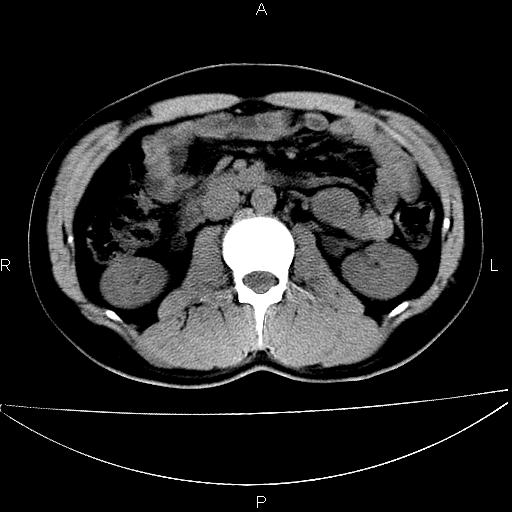

男 25岁 自述 尿频尿急,排尿困难20多天.无腰痛, b超说左肾盂轻度积水,左输尿管上端扩张.未见结石影. ct我看双侧肾盂轻度积水,双输尿管上端都扩张,大家看看能看见结石吗?

双肾轻度积水,双侧输尿管上段扩张(原因待查)。

双输尿管扩张下端未见高密度结石和输尿管晕轮征,不好说是结石.增强后如何?

双肾轻度积水,未见明确结石,薄层对结石检出率较高。

双肾盂及双输尿上段轻度积水,双输尿管未见明显结石影。